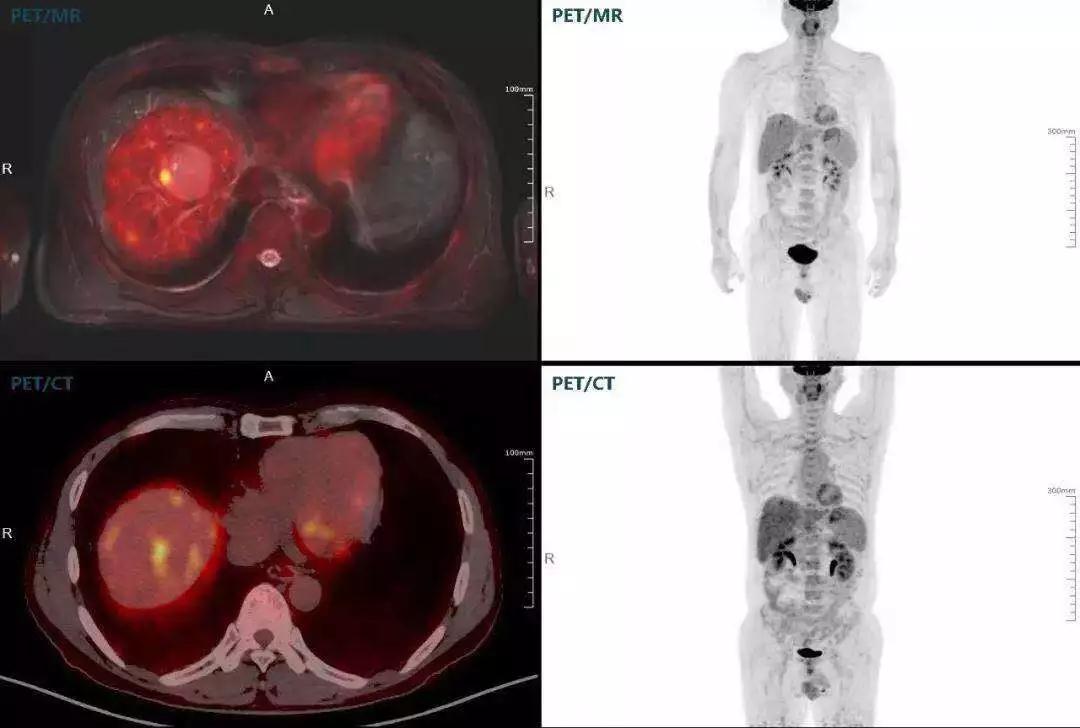

胰腺癌

中山醫(yī)院核醫(yī)學(xué)科在臨床實踐中發(fā)現(xiàn),基于聯(lián)影“時空一體”超清TOF PET/MR,不僅解剖信息和代謝信息能夠完美融合呈現(xiàn),同時精細(xì)展示局部病灶與周圍組織的復(fù)雜關(guān)系,并能全盤檢測病灶的全身轉(zhuǎn)移,為醫(yī)生臨床診斷提供更豐富信息。

(胰腺腫瘤,MR顯示胰腺體部信號異常,PET顯示稍高攝取,結(jié)構(gòu)改變和功能異常提示胰腺MT可能大。)

多發(fā)性骨髓瘤

中山醫(yī)院核醫(yī)學(xué)科基于聯(lián)影“時空一體”超清TOF PET/MR的融合顯像優(yōu)勢,進(jìn)行了大量的臨床掃描,發(fā)現(xiàn)多例由MGUS向多發(fā)性骨髓瘤轉(zhuǎn)變,并從中總結(jié)出了一定的共同征象,未來可能實現(xiàn)多發(fā)性骨髓瘤的早期篩查。此外,PET/MR在多發(fā)性骨髓瘤的療效評估方面,也存在顯著優(yōu)勢。

(男性,53歲。確診多發(fā)性骨髓瘤10月。經(jīng)過7周期VCD方案化療后,現(xiàn)行療效評價。)